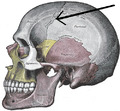

Sobo 1909 46 - Coronal suture.png

Superior view of the skull. ("Coronal suture" in red.)